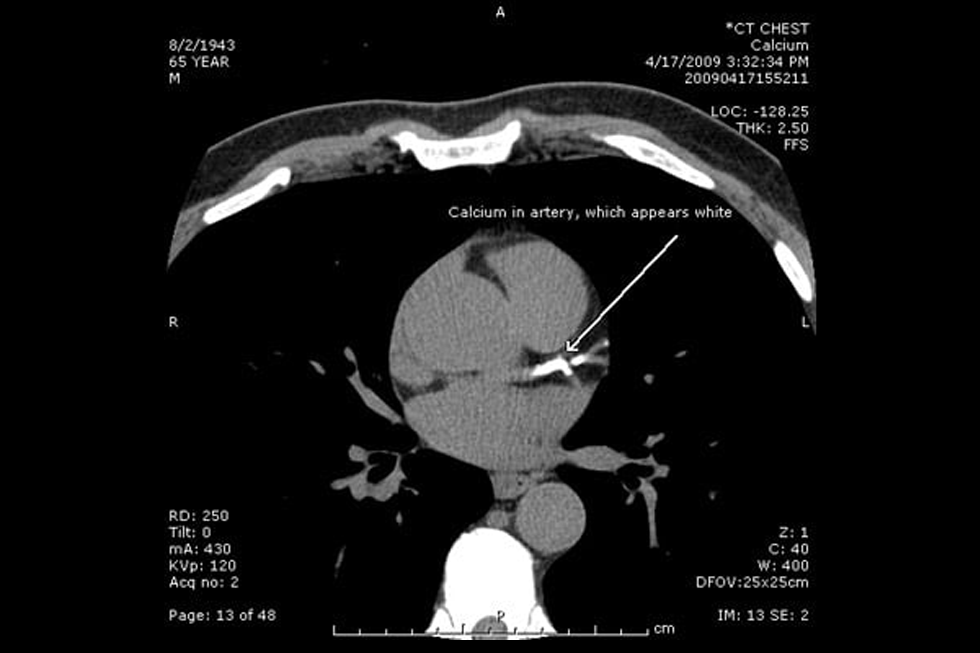

Coronary Calcium Scoring

A CT calcium scoring scan is a specialized, non-invasive test that uses computed tomography (CT) to detect and measure calcium deposits in the coronary arteries. Calcium buildup is a sign of coronary artery disease (CAD), which can lead to heart attacks. The scan provides a “calcium score” that helps doctors assess a person’s risk of heart disease before symptoms appear. It is quick, painless, and does not require contrast dye. CT calcium scoring is especially useful for evaluating risk in people with intermediate risk factors, such as high blood pressure, high cholesterol, or a family history of heart disease. Patient’s who have already had any form of coronary bypasses, stent placement, or grafting would not be ideal candidates.